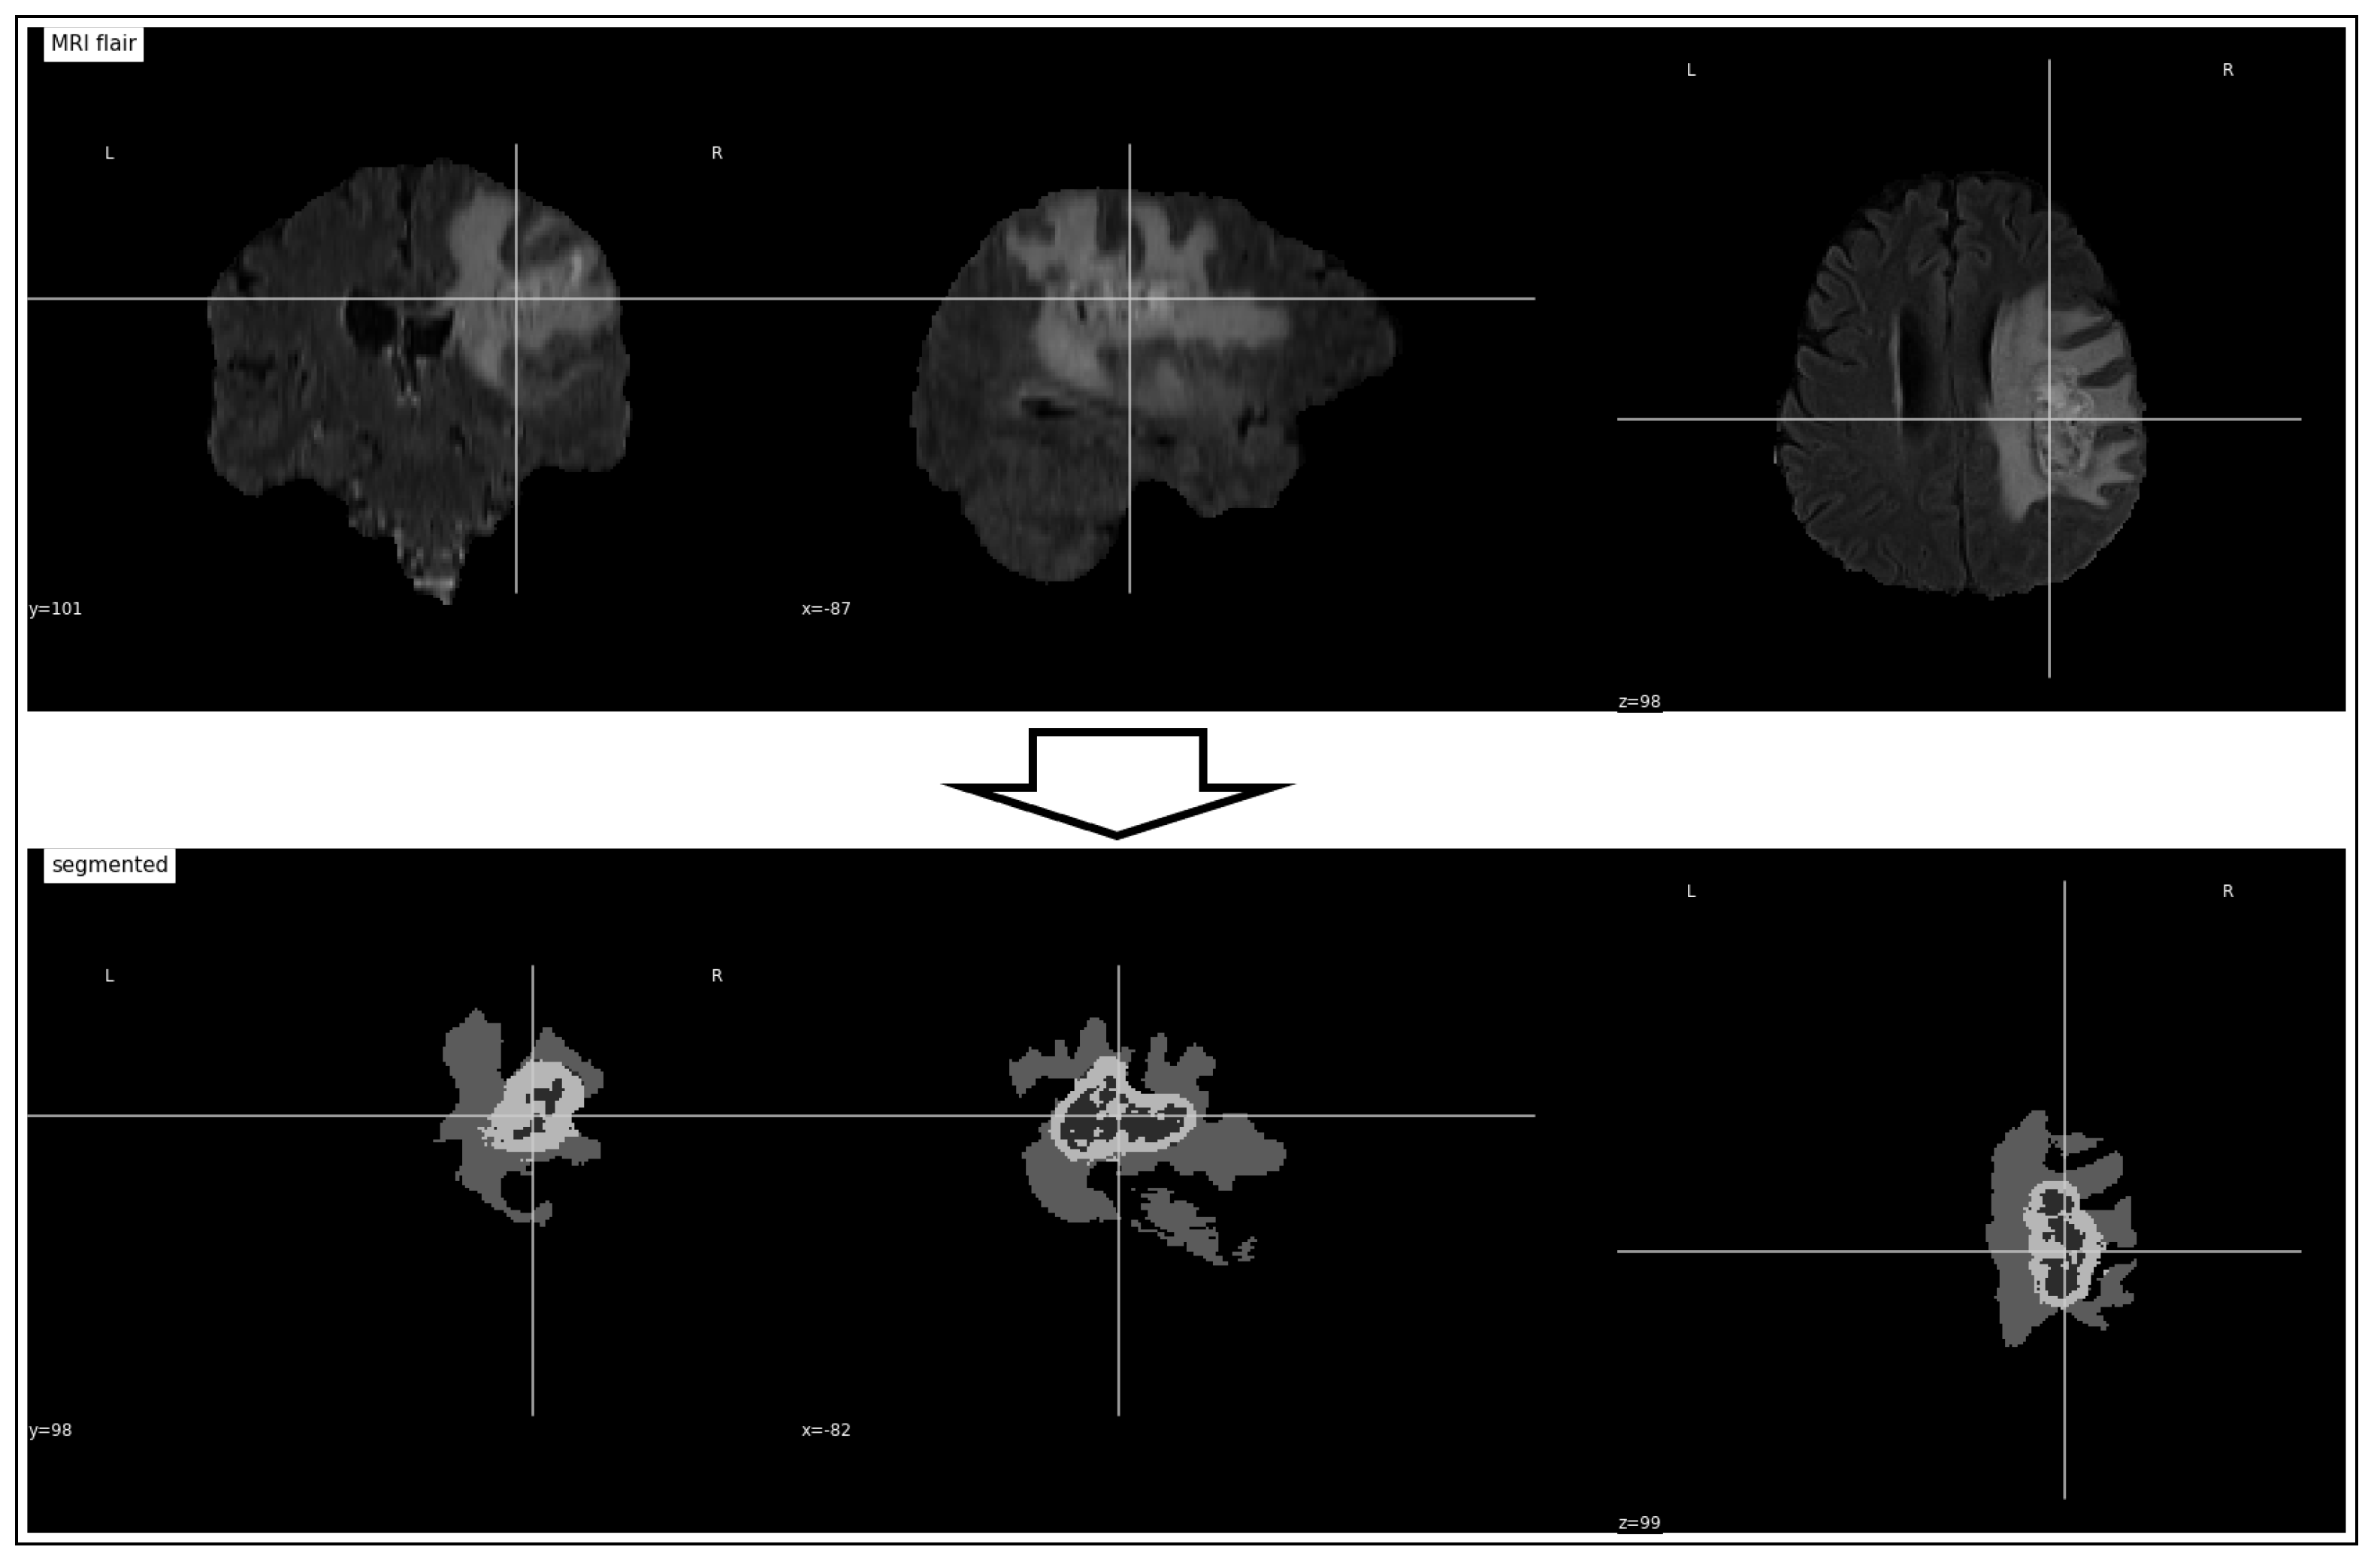

3.2. Tumor Identification

3.3. Tumor Volume Computation

4.3.1. Tumor Identification